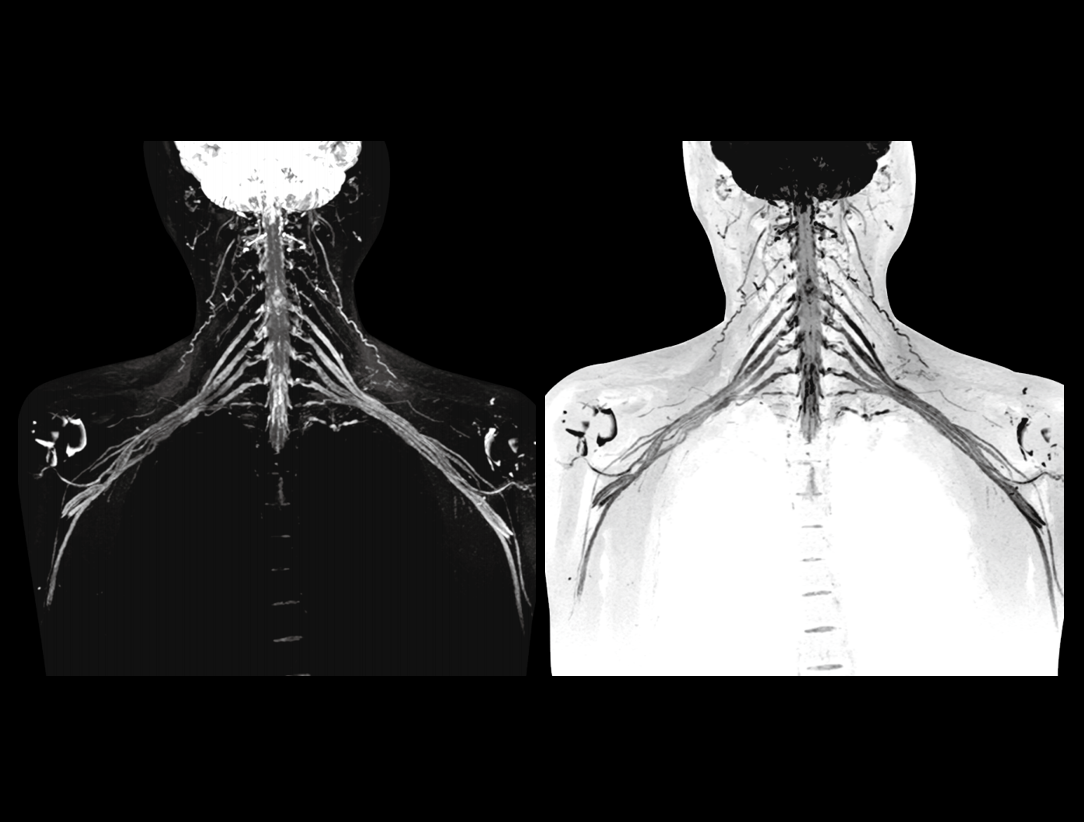

The 48 high-channel RF complements our integrated high-density coils, resulting insignificant image SNR increase.

The powerful 3.0T magnet uses a 170 cm short-magnet design to ensure high homogeneity of the magnetic field, which provides a solid foundation for fast imaging and excellent fat saturation over a large FOV, as well as outstanding off-center imaging.